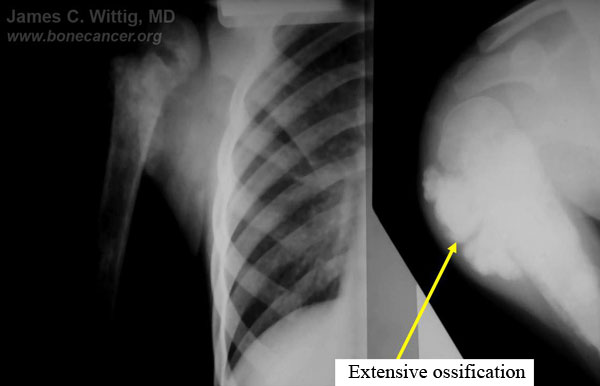

- Radiological studies may be useful in determining if the osteosarcoma has had a good response to chemotherapy preoperatively:

- X-rays and CT scans may show that intense ossification of the tumor occurs after a good response to preoperative chemotherapy

- The CT scan will often show a peripheral zone of calcification (egg shell around the tumor) when the tumor has had a good response

- MRI is not useful for evaluating response of osteosarcomas to preoperative chemotherapy

- Bone scan and/or thallium scan may be useful. Decreased uptake after preoperative chemotherapy compared to the uptake on initial diagnosis may be indicative of a good response

- Formal angiograms where dye is injected into the blood vessels of the extremity demonstrate the vascularity of the tumor. Viable tumors have significant blood vessels and therefore fill with the dye, causing a tumor blush. If an osteosarcoma has had a good response to chemotherapy, the vascularity will disappear and there will be little to no tumor blush. Angiogram is the gold standard for evaluating response to preoperative chemotherapy; however, it is not routinely performed because it is invasive.Estimating response before the surgical procedure may help with surgical planning and may also help in deciding whether a limb sparing surgery or an amputation should be performed. It is often not necessary to remove as much surrounding normal tissue around an osteosarcoma when the tumor has demonstrated a good response, as opposed to those tumors that do not demonstrate a good response.

- The final estimate of response to preoperative chemotherapy occurs when the specimen is surgically removed and analyzed by the pathologist. This estimate helps predict prognosis. A “good response” (usually greater than 90% of the tumor killed) has been correlated with approximately a 90% cure rate.